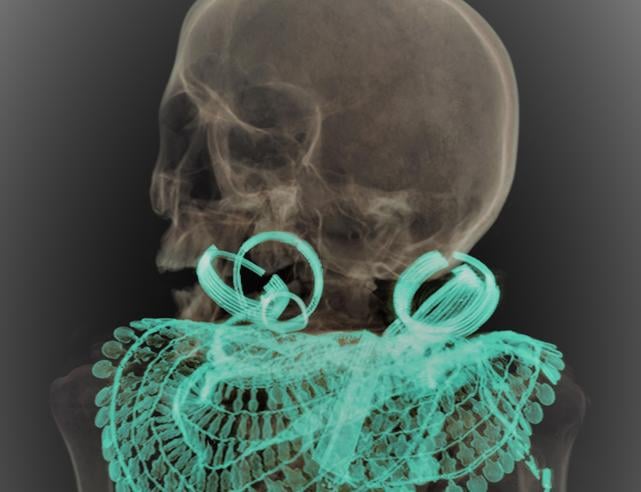

La descrizione della tomba fu talmente poco entusiasmante che Maspero concesse a Schiaparelli di tenere tutti i reperti ritrovati. Riportati quasi in sordina a Torino, sono rimasti pressoché lasciati a loro stessi per decenni, fino al 2016, quando un fondo di ricerca svizzero (!) dedicato al rituale dei vasi canopici ma anche al riconoscimento delle mummie egizie ha permesso di analizzare anche dei resti umani che erano stati ritrovati nella tomba. Per essere precisi: un ginocchio pressoché completo (parte distale del femore, patella e parte prossimale della tibia), la parte distale di un secondo femore e quella prossimale di una seconda tibia.

Le gambe appartenevano ad una donna, di età apparente tra i 40 ed i 50 anni, affetta da una minima osteoporosi probabilmente associata a deficienza di Vitamina D (ipotizzata da scarsa esposizione solare, come nel caso di chi non effettui lavori all’aperto). Tracce di arteriosclerosi (calcificazione delle arterie tibiali) hanno confermato l’età presunta. Le dimensioni delle ossa suggeriscono un’altezza intorno ai 165 ± 2.5 centimetri, notevoli per l’epoca (la media in Egitto era di 156 cm per le donne nel Nuovo Regno) e di corporatura molto snella.

L’analisi radiografica delle due gambe che ha permesso di determinarne età, corporatura ed altezza presunta. A destra: evidenziate le calcificazioni delle arterie tibiali ad ulteriore conferma dell’età presunta al momento del decesso

L’altezza presunta è stata confermata anche da un paio di sandali, misura 39, trovati nella tomba. I sandali risultano essere stati usati (e non oggetti ornamentali); l’impronta dell’alluce sinistro conferma l’altezza presunta.